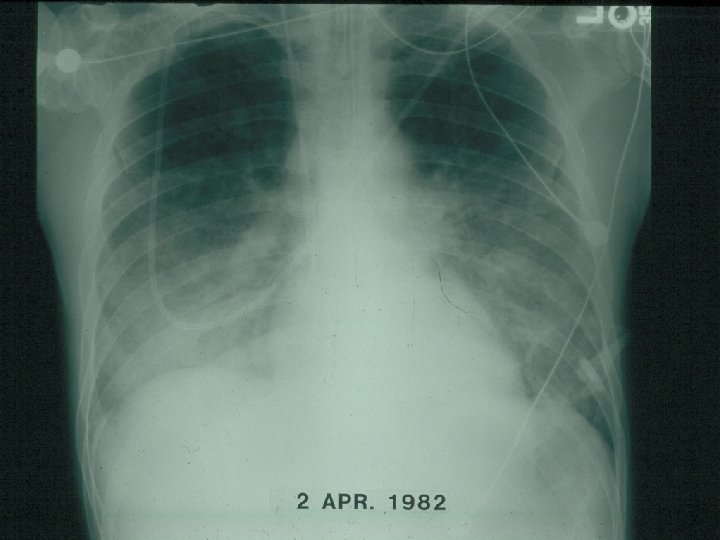

Belaynesh’s Laboratory Results • • WBC TLC Hgb Gram stain AFB HIV serology CD 4 CXR 2500/mm 3 750/mm 3 12 g/dl negative 3 x positive pending as follows

PCP Chest Radiograph

Discussion • How do these results change your differential diagnosis? • How would you manage this patient?

Focused Differential Diagnosis • PCP • Pulmonary tuberculosis (atypical appearance) in late stage HIV disease

Pneumocystis Jiroveci Pneumonia • Most humans infected early in life • Diagnosis via induced sputum or bronchoalveolar lavage (bronchoscopy) – Stains with Wright-Giemsa, methenamine silver, and direct immunofluorescence • Typical presentation – Non-productive cough – Exertional dyspnea – Gradual fever